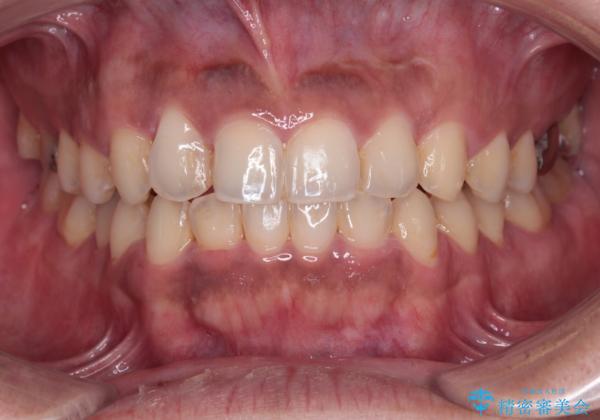

デコボコを治したい インビザラインによる矯正治療

途中2年強の来院がなく、改善されていたデコボコが元に戻ったり、装着時間が不足しており前歯のデコボコは十分に改善することはできませんでしたが、5年間の有効期限内で可能な限り歯列を整えることができました。